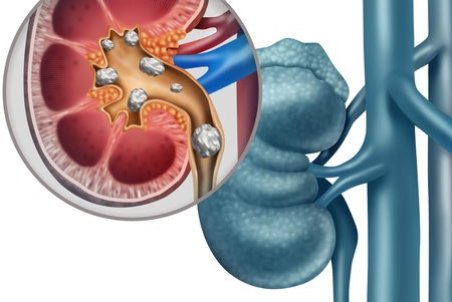

سنگ کلیه جسم سختی است که از موادشیمیایی در ادرار تشکیل شده. انواع متعددی دارد،اما همه دارای علائم مشابهی هستند که می تواند بسیار دردناک باشند،به ویژه اگر سنگ کلیه به مرور زمان رشد کرده باشد.

یکی از مشکلات کلیوی رایج سنگ کلیه می باشد که از مواد معدنی و نمکی در دستگاه ادراری تشکیل می شود. یکی از راه هایی که مورد توجه افراد بسیاری قرار می گیرد استفاده از داروهای گیاهی برای سنگ کلیه می باشد که در این مقاله به معرفی آنها می پردازیم.

تجمع بیش از حد املاح در کلیهها میتواند منجر به تشکیل سنگهایی به شکل کریستال شود که اگر دفع نشوند، میتوانند عوارضی چون عفونت یا آسیبهای کلیوی را بهدنبال داشته باشند.

معمولاً سنگهای کلیه کوچک، بدون بروز علائم و مشکلات خاصی دفع میشوند اما سنگهای بزرگتر در مجاری ادراری لانه میکنند و منجر به درد میشوند؛ اگر این سنگها دفع نشوند، میتوانند عوارضی چون عفونت یا آسیبهای کلیوی را بهدنبال داشته باشند.